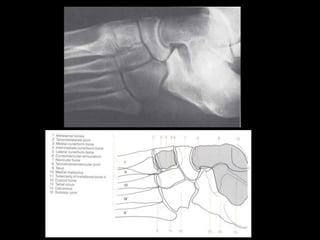

This document provides an overview of normal musculoskeletal imaging. It discusses basic x-ray concepts and densities. It then reviews normal anatomy as seen on x-rays of the skull, spine, pelvis, chest, and extremities. Key anatomical structures are labeled on example x-rays for the shoulder, hip, knee, and foot. Quizzes are included to test recognition of anatomical structures and patient age based on x-rays.